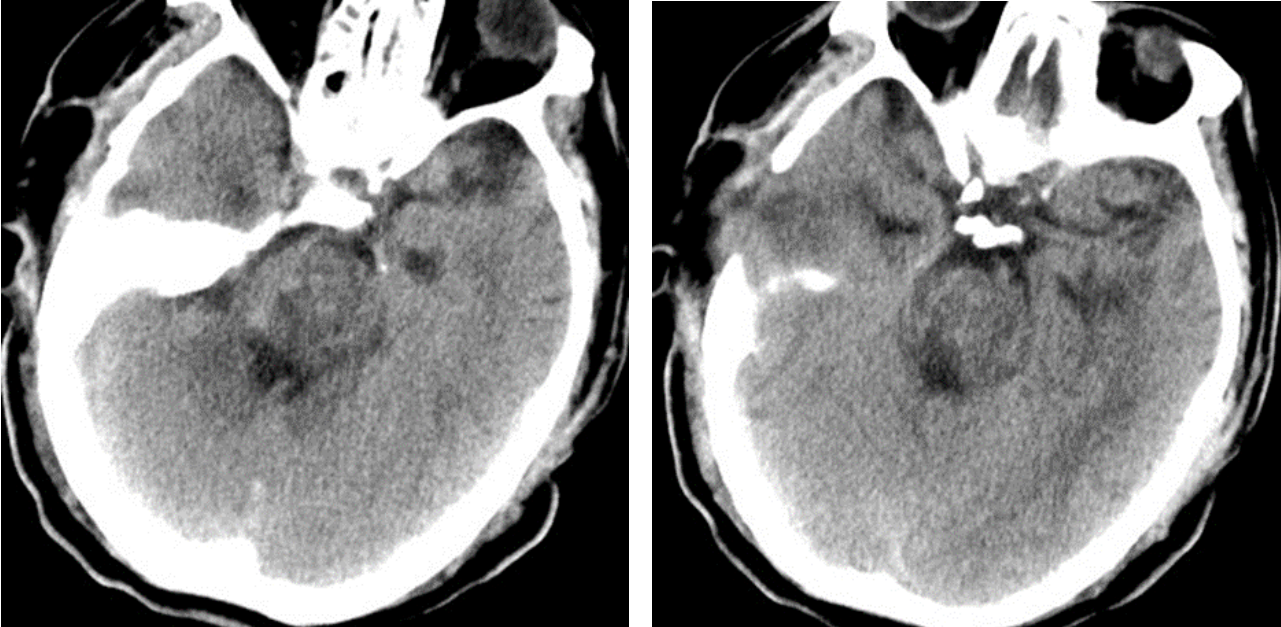

在手術(shù)室、麻醉科的積極配合下,整個(gè)手術(shù)團(tuán)隊(duì)分工有序、緊密配合,采用顳下入路,切開(kāi)小腦幕,暴露并保護(hù)滑車(chē)神經(jīng)、三叉神經(jīng)、大腦后動(dòng)脈,應(yīng)用顯微鏡在橋腦三叉神經(jīng)上區(qū)域通過(guò)4毫米的通道,清除腦干內(nèi)10余毫升出血,并對(duì)原發(fā)出血部位妥善止血。經(jīng)過(guò)3個(gè)多小時(shí)的精細(xì)操作,在確保最小腦損傷的情況下清除血腫,術(shù)中各項(xiàng)監(jiān)測(cè)指標(biāo)平穩(wěn),術(shù)后復(fù)查頭顱CT顯示血腫清除滿意。術(shù)后經(jīng)過(guò)重癥監(jiān)護(hù)室積極治療,患者平穩(wěn)渡過(guò)中樞性高熱、嚴(yán)重肺部感染、營(yíng)養(yǎng)低下等并發(fā)癥期,各項(xiàng)生命體征逐步平穩(wěn),對(duì)外界刺激有適當(dāng)反應(yīng),術(shù)后13天轉(zhuǎn)入普通病房繼續(xù)康復(fù)促醒治療。

術(shù)后患者顱腦CT: